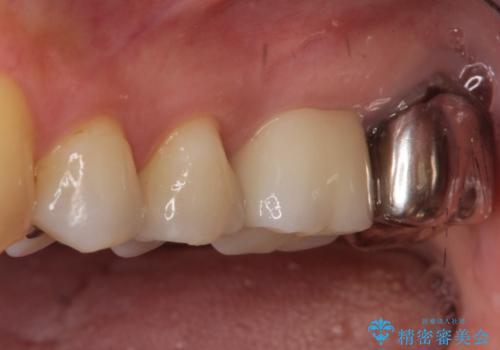

【根管治療】未処置根管を有した歯の再根管治療

- 定期検診にて虫歯を見つけたため、根管治療からオールセラミッククラウンによる修復治療を行いました。

上顎第一大臼歯の近心根にはほとんどの場合、神経の管が二本あることが多いです。顕微鏡を用いることで見逃すことなく治療が行えました。